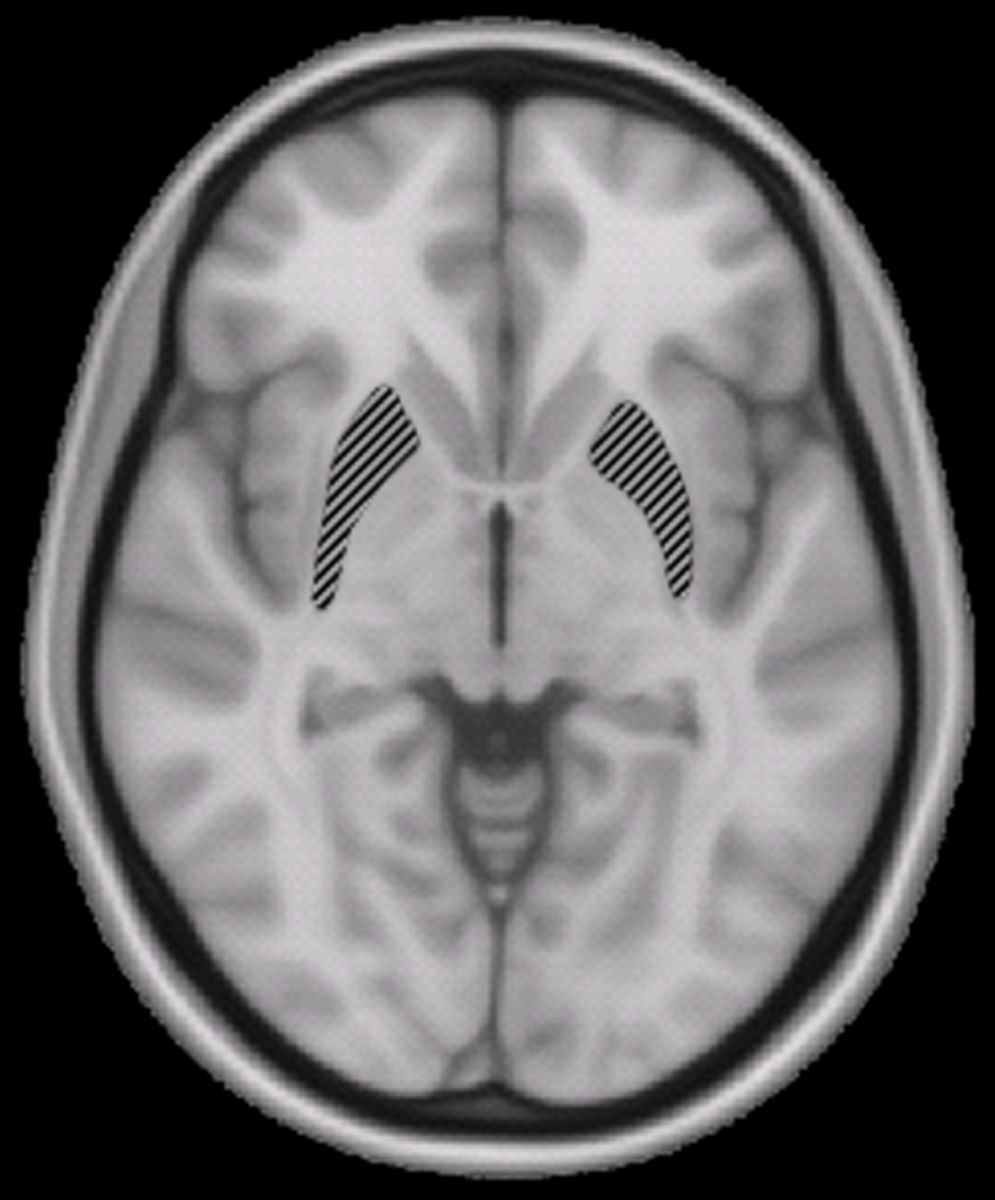

Putamen

By Woutergroen (Own work) [Public domain], via Wikimedia Commons